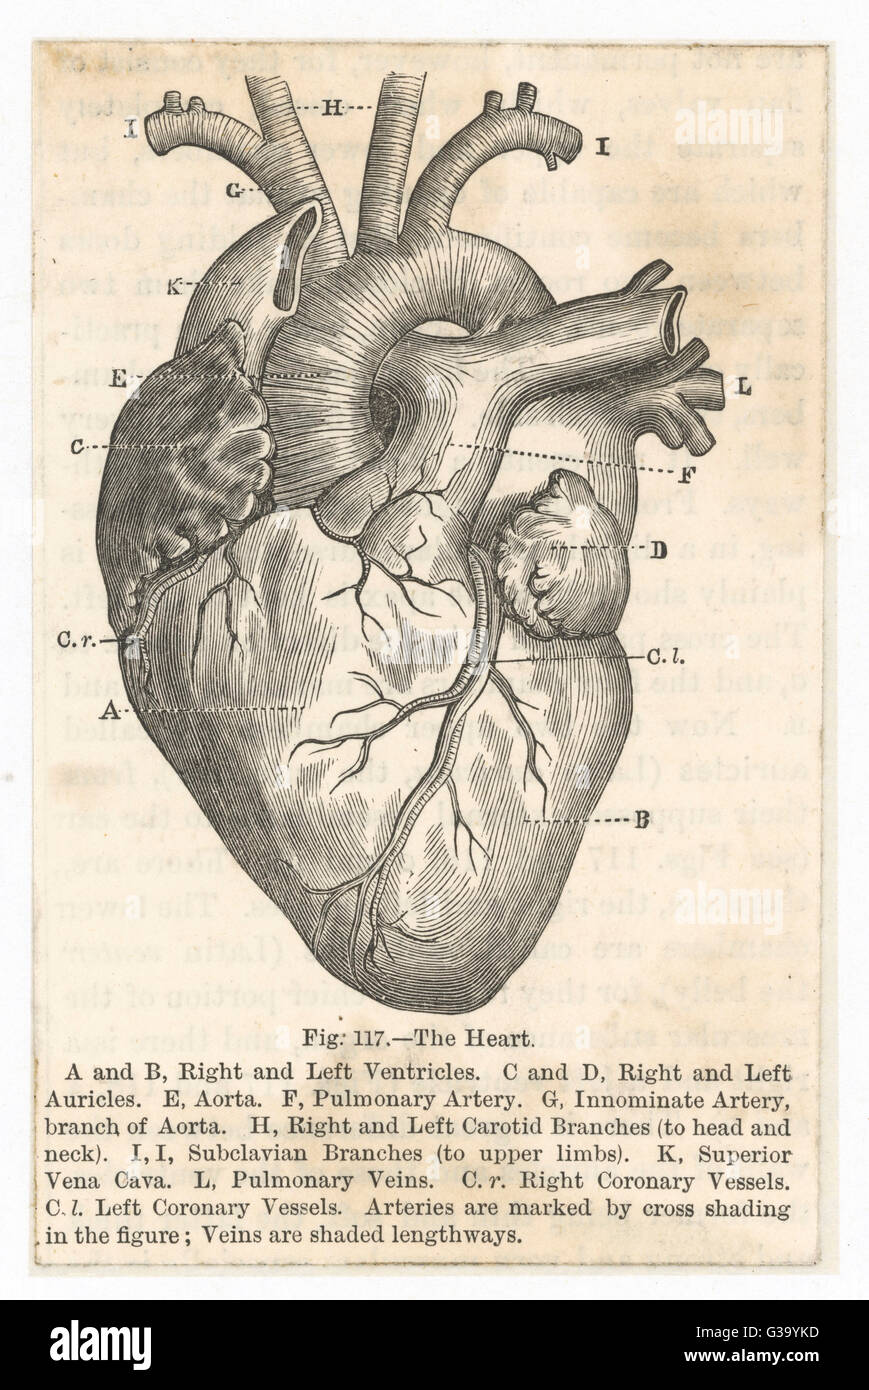

Diagram illustration of the human heart Stock Photohttps://www.alamy.com/image-license-details/?v=1https://www.alamy.com/stock-photo-diagram-illustration-of-the-human-heart-105325457.html

Diagram illustration of the human heart Stock Photohttps://www.alamy.com/image-license-details/?v=1https://www.alamy.com/stock-photo-diagram-illustration-of-the-human-heart-105325457.htmlRMG39YKD–Diagram illustration of the human heart